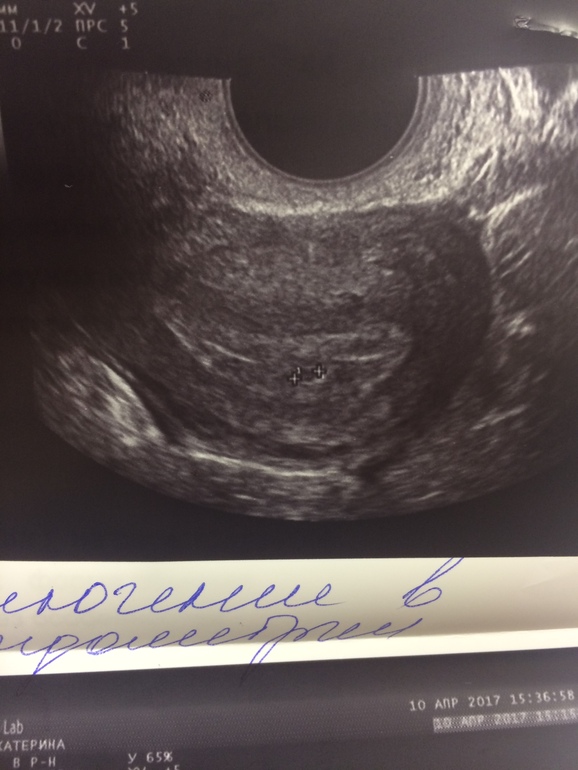

Девочки, милые, я тут новенькая, помогите разобраться....Сегодня ( 4 недели, 4 дня) была на УЗИ, плодного яйца молоденькая узист не увидела..Посмотрите на фото.... она поставила под вопрос саму беременность. Хгч 600. ( росло с 50ти)